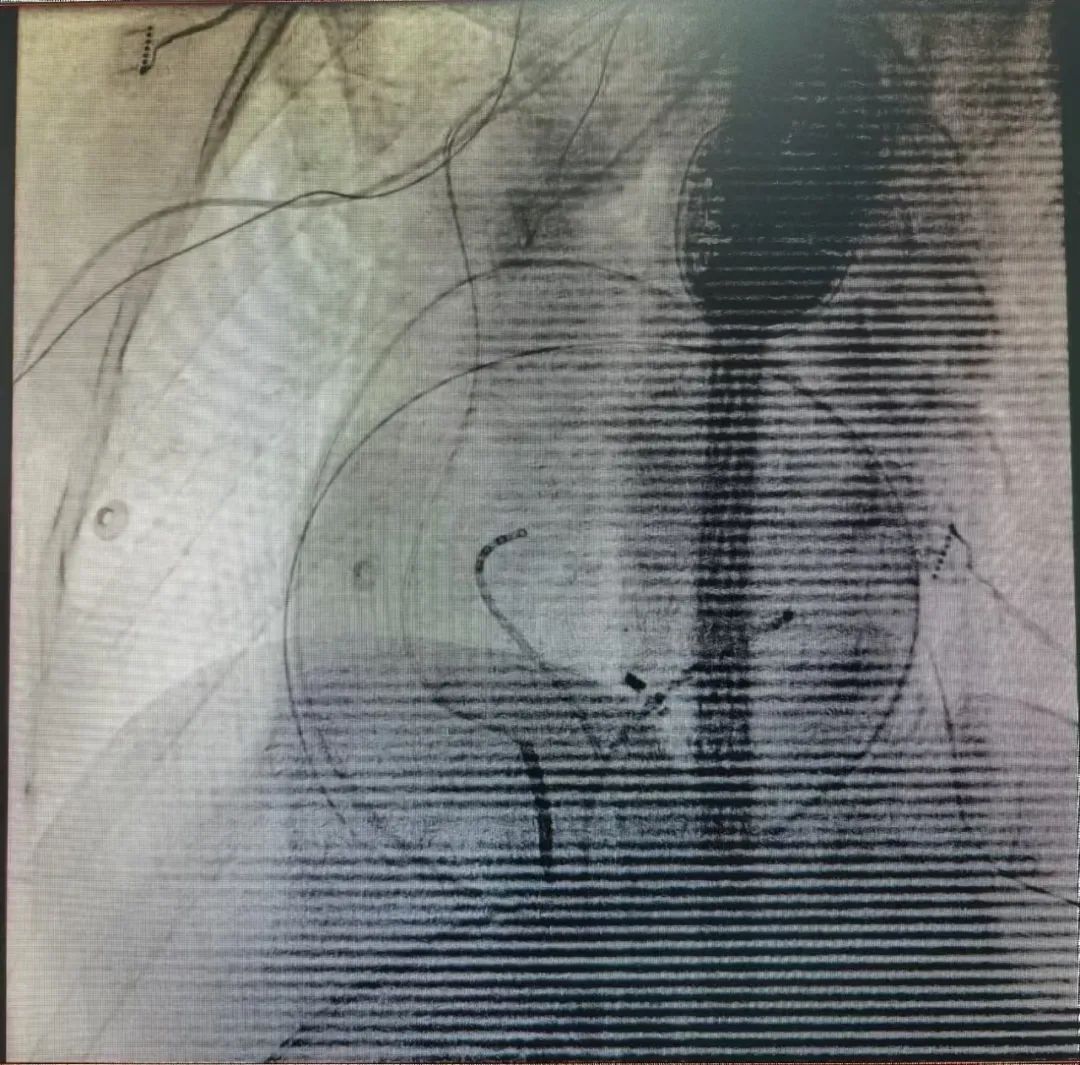

手术在导管室进行。在导管室的配合下,解新星主任首先穿刺股动脉进入左心室行心内膜标测,如术前所料,患者心内膜电压正常,无明显异常电位,且室早发作时心内膜激动不提前,高度提示心外膜起源可能。干性心包穿刺选择剑突下途径,多体位X线透照确定穿刺方向,穿刺针顺利突破壁层心包,送入导丝确定穿刺成功。心外膜标测显示左心室下壁中部有片状低电压疤痕区,室早时局部电位提前,局部起搏与患者自发室性早搏匹配良好,随即对低电压区及异常电位区行片状消融,术后反复诱发不能诱发室速。术后未见心包积液,手术顺利结束。目前该患者已顺利出院。